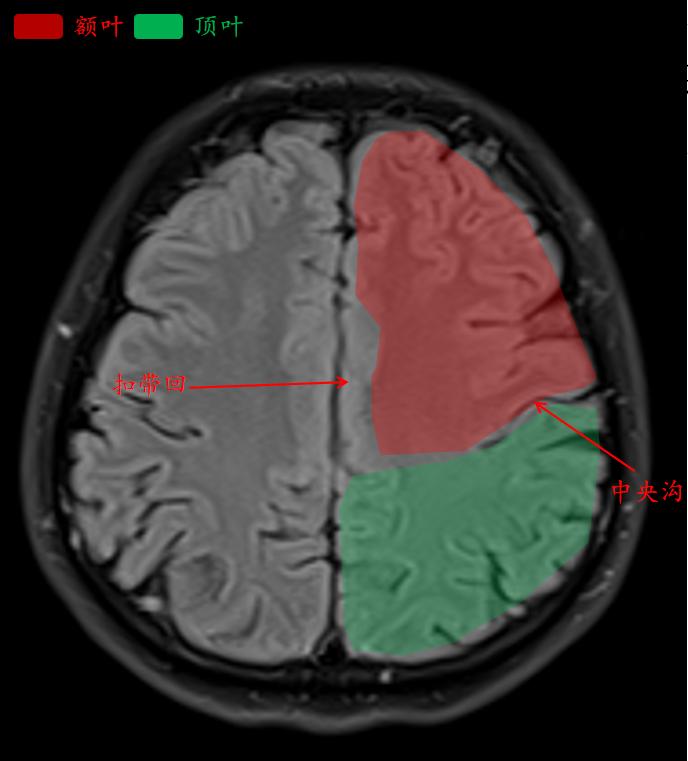

这就是常规医院扫描的t2-flair的相似层厚层间距的图像。

中央沟是额叶和顶叶的分界线。

额叶:主要功能是控制随意运动、计算力、语言、情感(淡漠)和智能,与内脏活动和共济运动有关。

顶叶的功能与邻近结构有重叠。